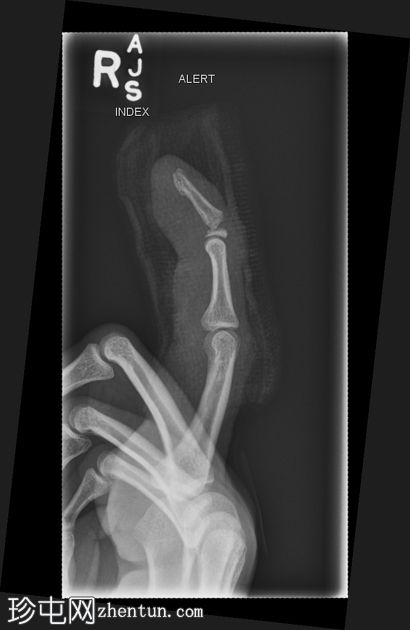

侧位片

右食指远节指骨基底部横向移位骨折,伴有背侧成角,最符合成人型Seymour骨折。指尖小骨折。

本例为罕见的成人型Seymour骨折,此类骨折通常发生于骨骼未成熟的远节指骨骨骺处。